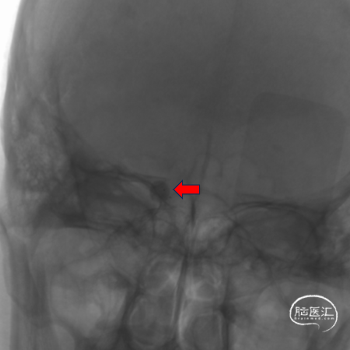

栓塞金球囊到位。

栓塞金球囊半充盈堵塞瘘口,ICA海绵窦段以远显影。

栓塞金球囊全充盈堵塞瘘口,ICA海绵窦段以远显影良好,但瘘口有少量侧漏。

10min后显示瘘口侧漏消失。